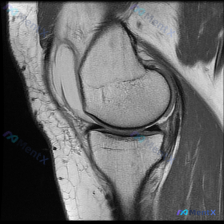

刚整理完这例踝关节MRI读片资料,分享一下完整的分析思路,这个病例的影像特征其实挺典型的,一起看看。 病例影像基础信息 这是一张踝关节MRI T1加权序列的正中矢状位图像,图像质量清晰,结构对比度好,无明显运动伪影,可以清晰辨认胫骨远端、距骨、跟骨、舟骨等骨性结构。 核心阳性发现 1. 骨信号异常:...